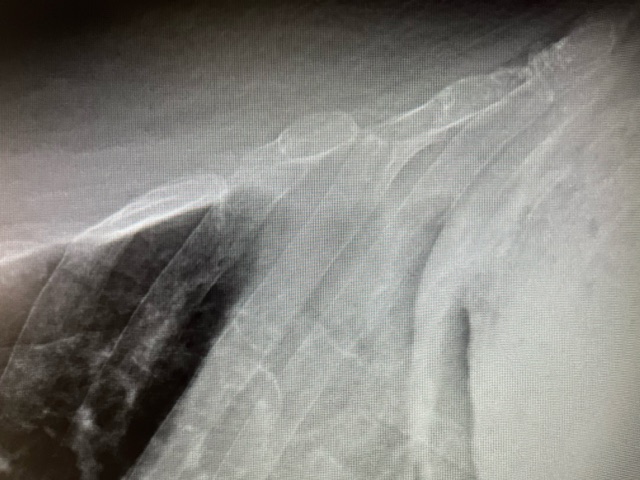

Otras pruebas complementarias realizadas (si existen)

Posteriormente, se solicitó una radiografía de parrilla costal de carácter urgente que confirmó dichos hallazgos.

Juicio clínico, diagnóstico diferencial, concordancia con el hospital (en su caso)

Por lo tanto, se trata de un caso de una fractura costal de 7-8º arco costal izquierdo tras caída casual.